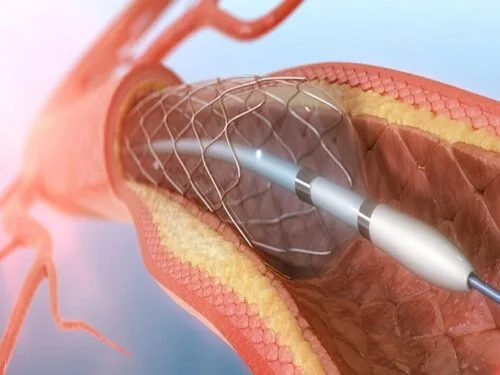

- عمل پیشرفته و موفقیتآمیز تاوی (TAVI)در ایران، در شهر مقدس مشهد توسط دکتر سید محسن جهرمی مقدم

- تنگی دریچه آئورت

- جراحی دریچه قلب

- آنژیوپلاستی کرونری